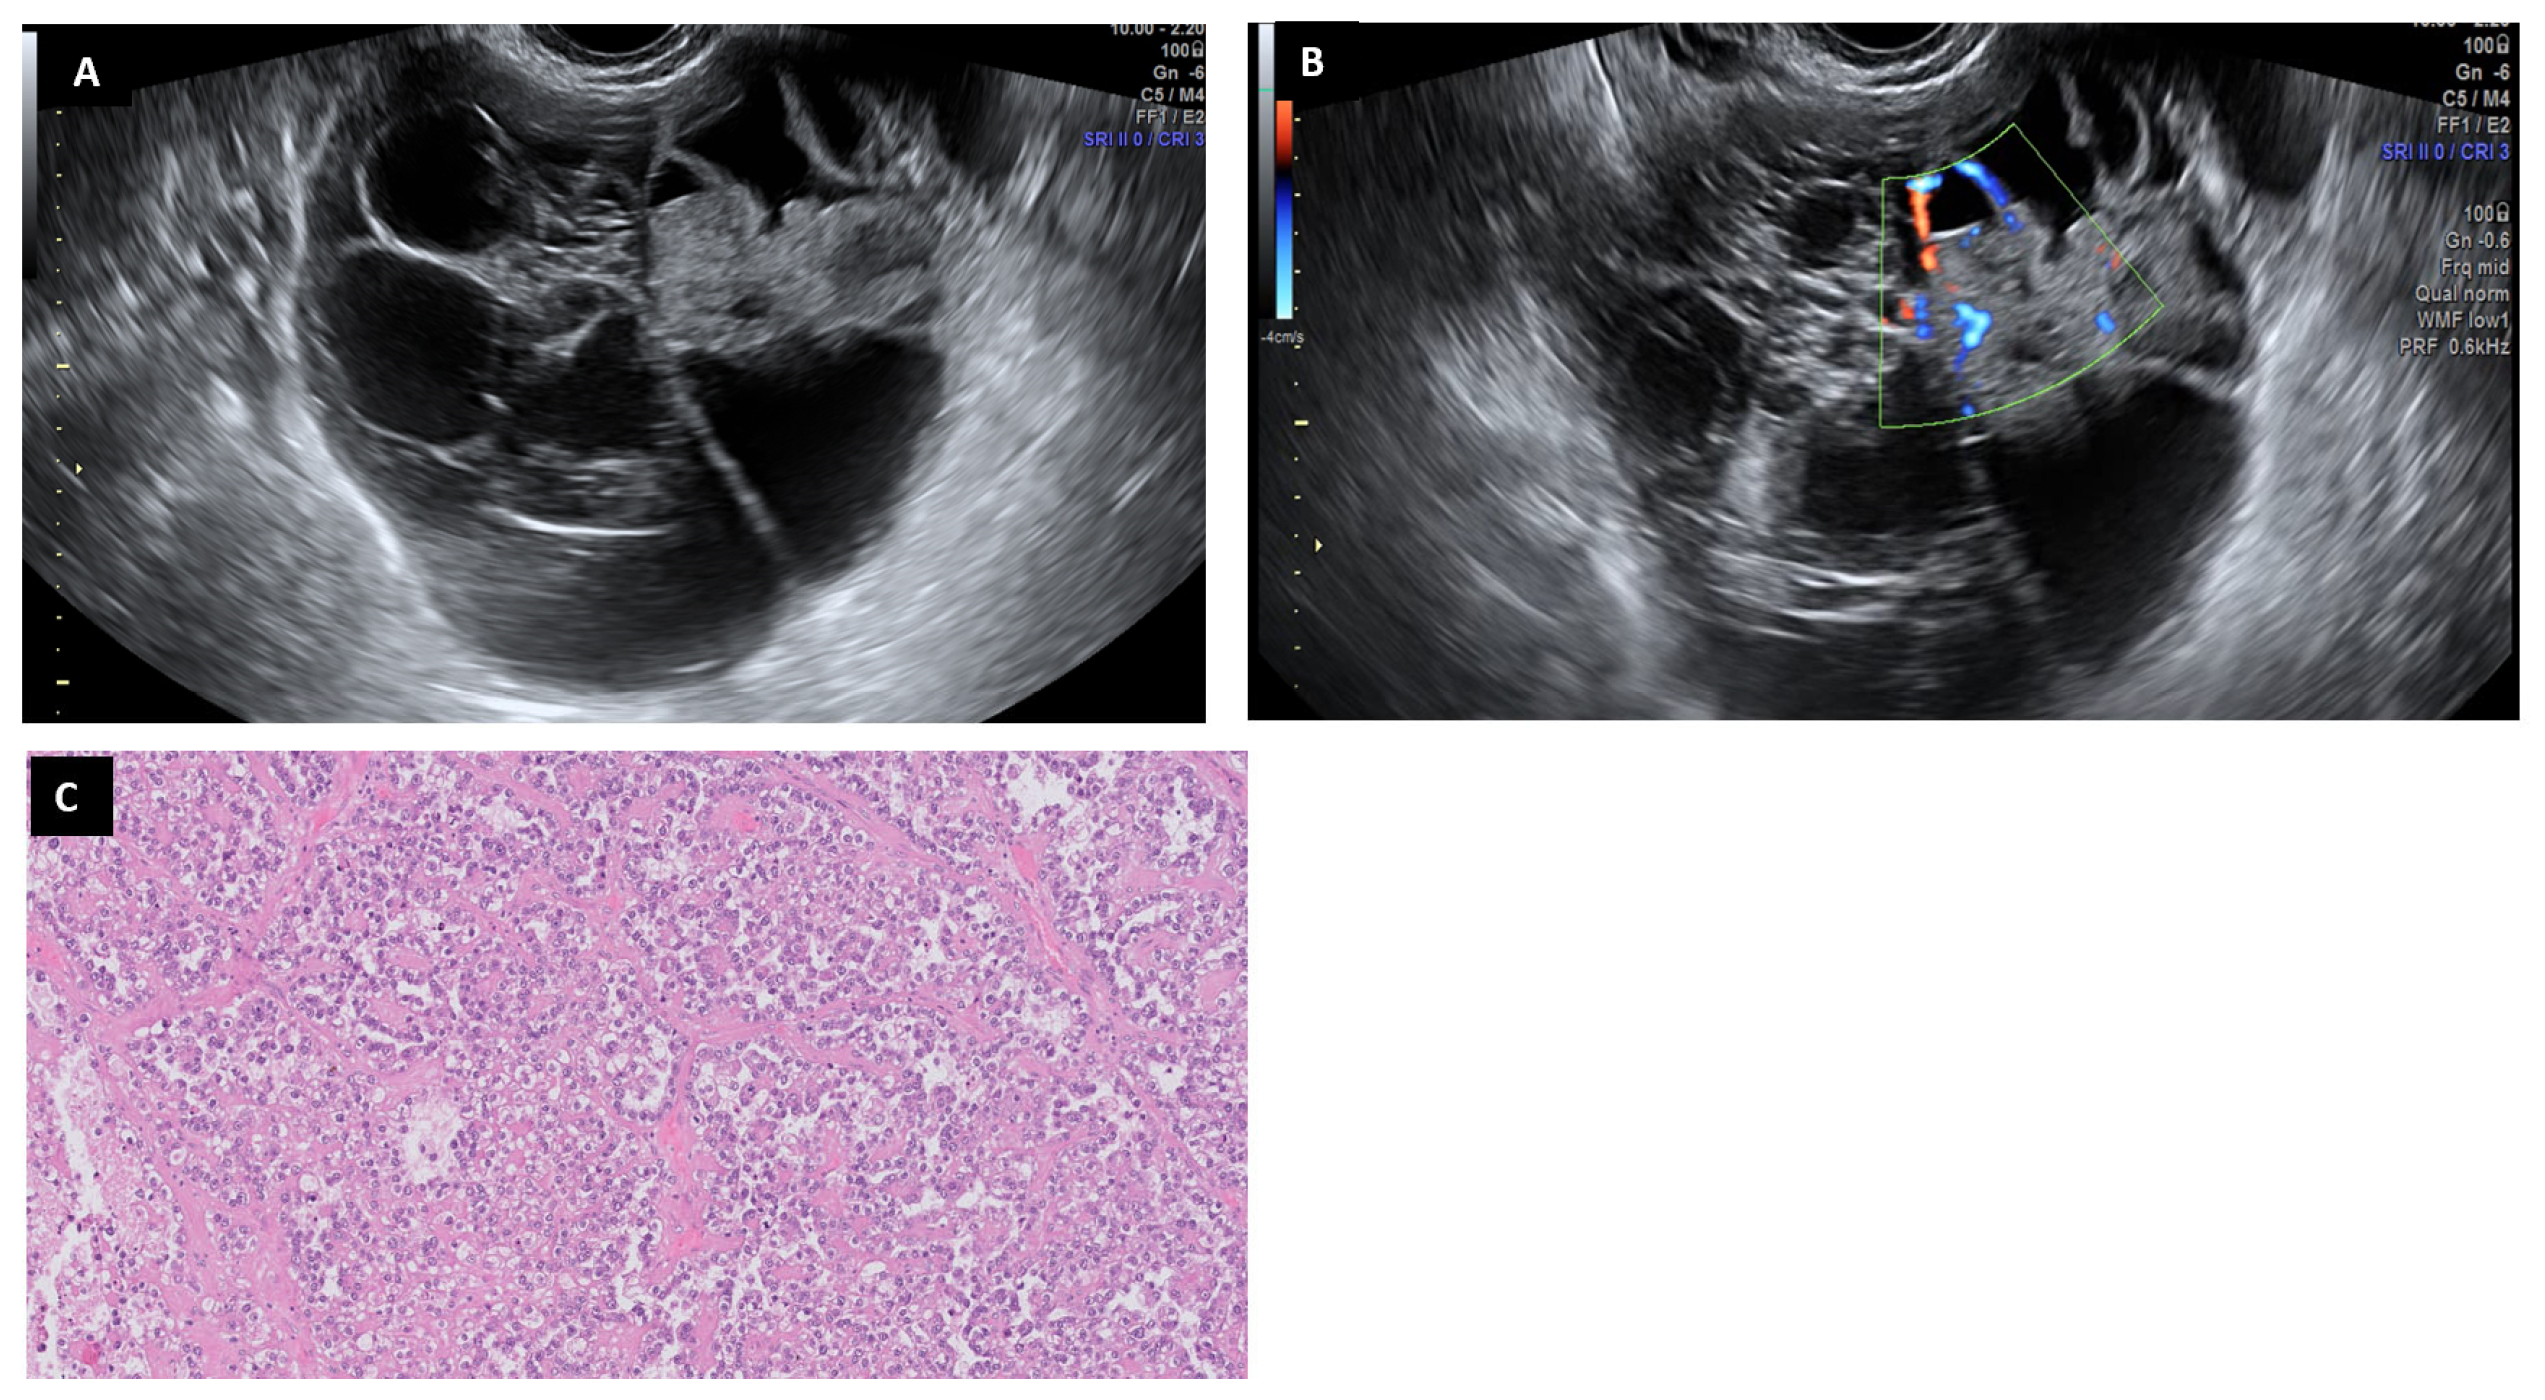

6.9. Clear Cell Carcinoma

6.10. Endometrioid Carcinoma